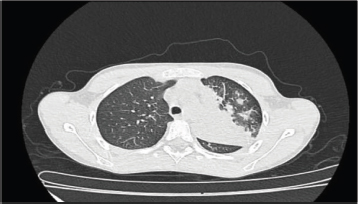

Respiratory findings were observed in 23% of patients, including crackles, wheezing, rhonchi, crepitations, reduced air entry and exit during inspiration and expiration, and decreased vesicular breath sounds on physical examination. Of these, isolated rhonchi, detected in 6 (26.1%) of the 23 patients, were the most common pulmonary finding. Chest X-rays were performed on 7% of the study population, revealing pneumonia in three (3) cases—one in the right lung and two in the left lung (Figure 2). One patient with left lung pneumonia also required a chest CT scan (Figure 3).

Figure 3. Pulmonary consolidation with multiple foci in the left upper and lower lobes